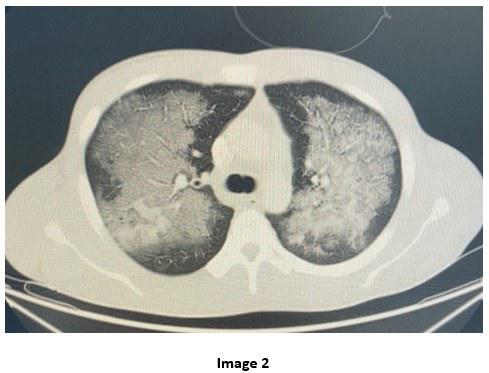

A 28-year-old male with Hepatitis C and history of substance abuse including synthetic marijuana and crack cocaine who presented with acute onset shortness of breath, hemoptysis and chest tightness of 2 hours duration. Upon evaluation, he was found to be hypoxic with SpO2= 80% on non-rebreather mask (FiO2= 100, Flow= 15L/min) requiring intubation. Complete Blood Count (CBC) revealed leukocytosis WBC= 21.13 x10 3 with neutrophilic predominance (92%) and left shifting of +1. Renal panel without major electrolyte disturbance or acid base disorders. The urine toxicology positive for Cocaine and THC. Mycoplasma IgM titers, Influenza A and B titers and Mycobacterium tuberculosis smear and culture were all negative. He was treated with systemic corticosteroid, scheduled bronchodilators and started on broad spectrum antibiotics. He was admitted to the Medical Intensive Care Unit. The chest X-ray and chest CT obtained are shown below